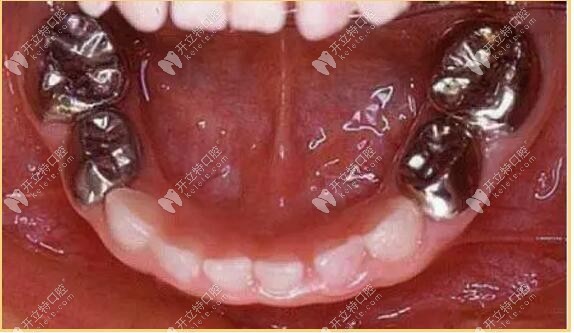

二、金屬預(yù)成冠

又叫不銹鋼冠,常用語乳牙磨牙治療,兒童不銹鋼乳牙欲成歡是一個預(yù)先塑性的、與牙齒貼合度比較高的金屬牙冠,用來套在乳牙上,保護牙齒并加強牙齒的強度,確保正常被恒壓替換。

金屬預(yù)成冠

金屬預(yù)成冠能有效防止充填物的脫落、繼發(fā)齲的產(chǎn)生和牙體組織的折裂,保證兒童的頜骨生長和繼承恒壓的替換。